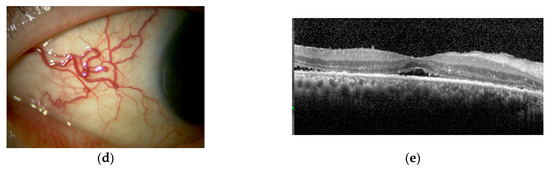

2.2.1. Case Presentations of Severe Posterior Scleritis Treated with Molecularly Targeted Therapies

Case 1

Case 2

Case 3